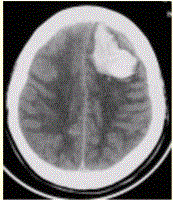

问题 患者男,45岁,突发剧烈头痛伴呕吐30min。既往有高血压病史,平日血压为(190~160)/(100~110)mmHg。查体:右侧肢体肌力Ⅱ级,无颈项强直。CT表现如下图。 脑血肿的血红蛋白的动态演变规律是

选项 A.含氧血红蛋白-正铁血红蛋白-脱氧血红蛋白-含铁血黄素 B.含氧血红蛋白-脱氧血红蛋白-正铁血红蛋白-含铁血黄素 C.含氧血红蛋白-脱氧血红蛋白-含铁血黄素-正铁血红蛋白 D.含氧血红蛋白-正铁血红蛋白-含铁血黄素-脱氧血红蛋白 E.含氧血红蛋白-含铁血黄素-脱氧血红蛋白-正铁血红蛋白

答案 B